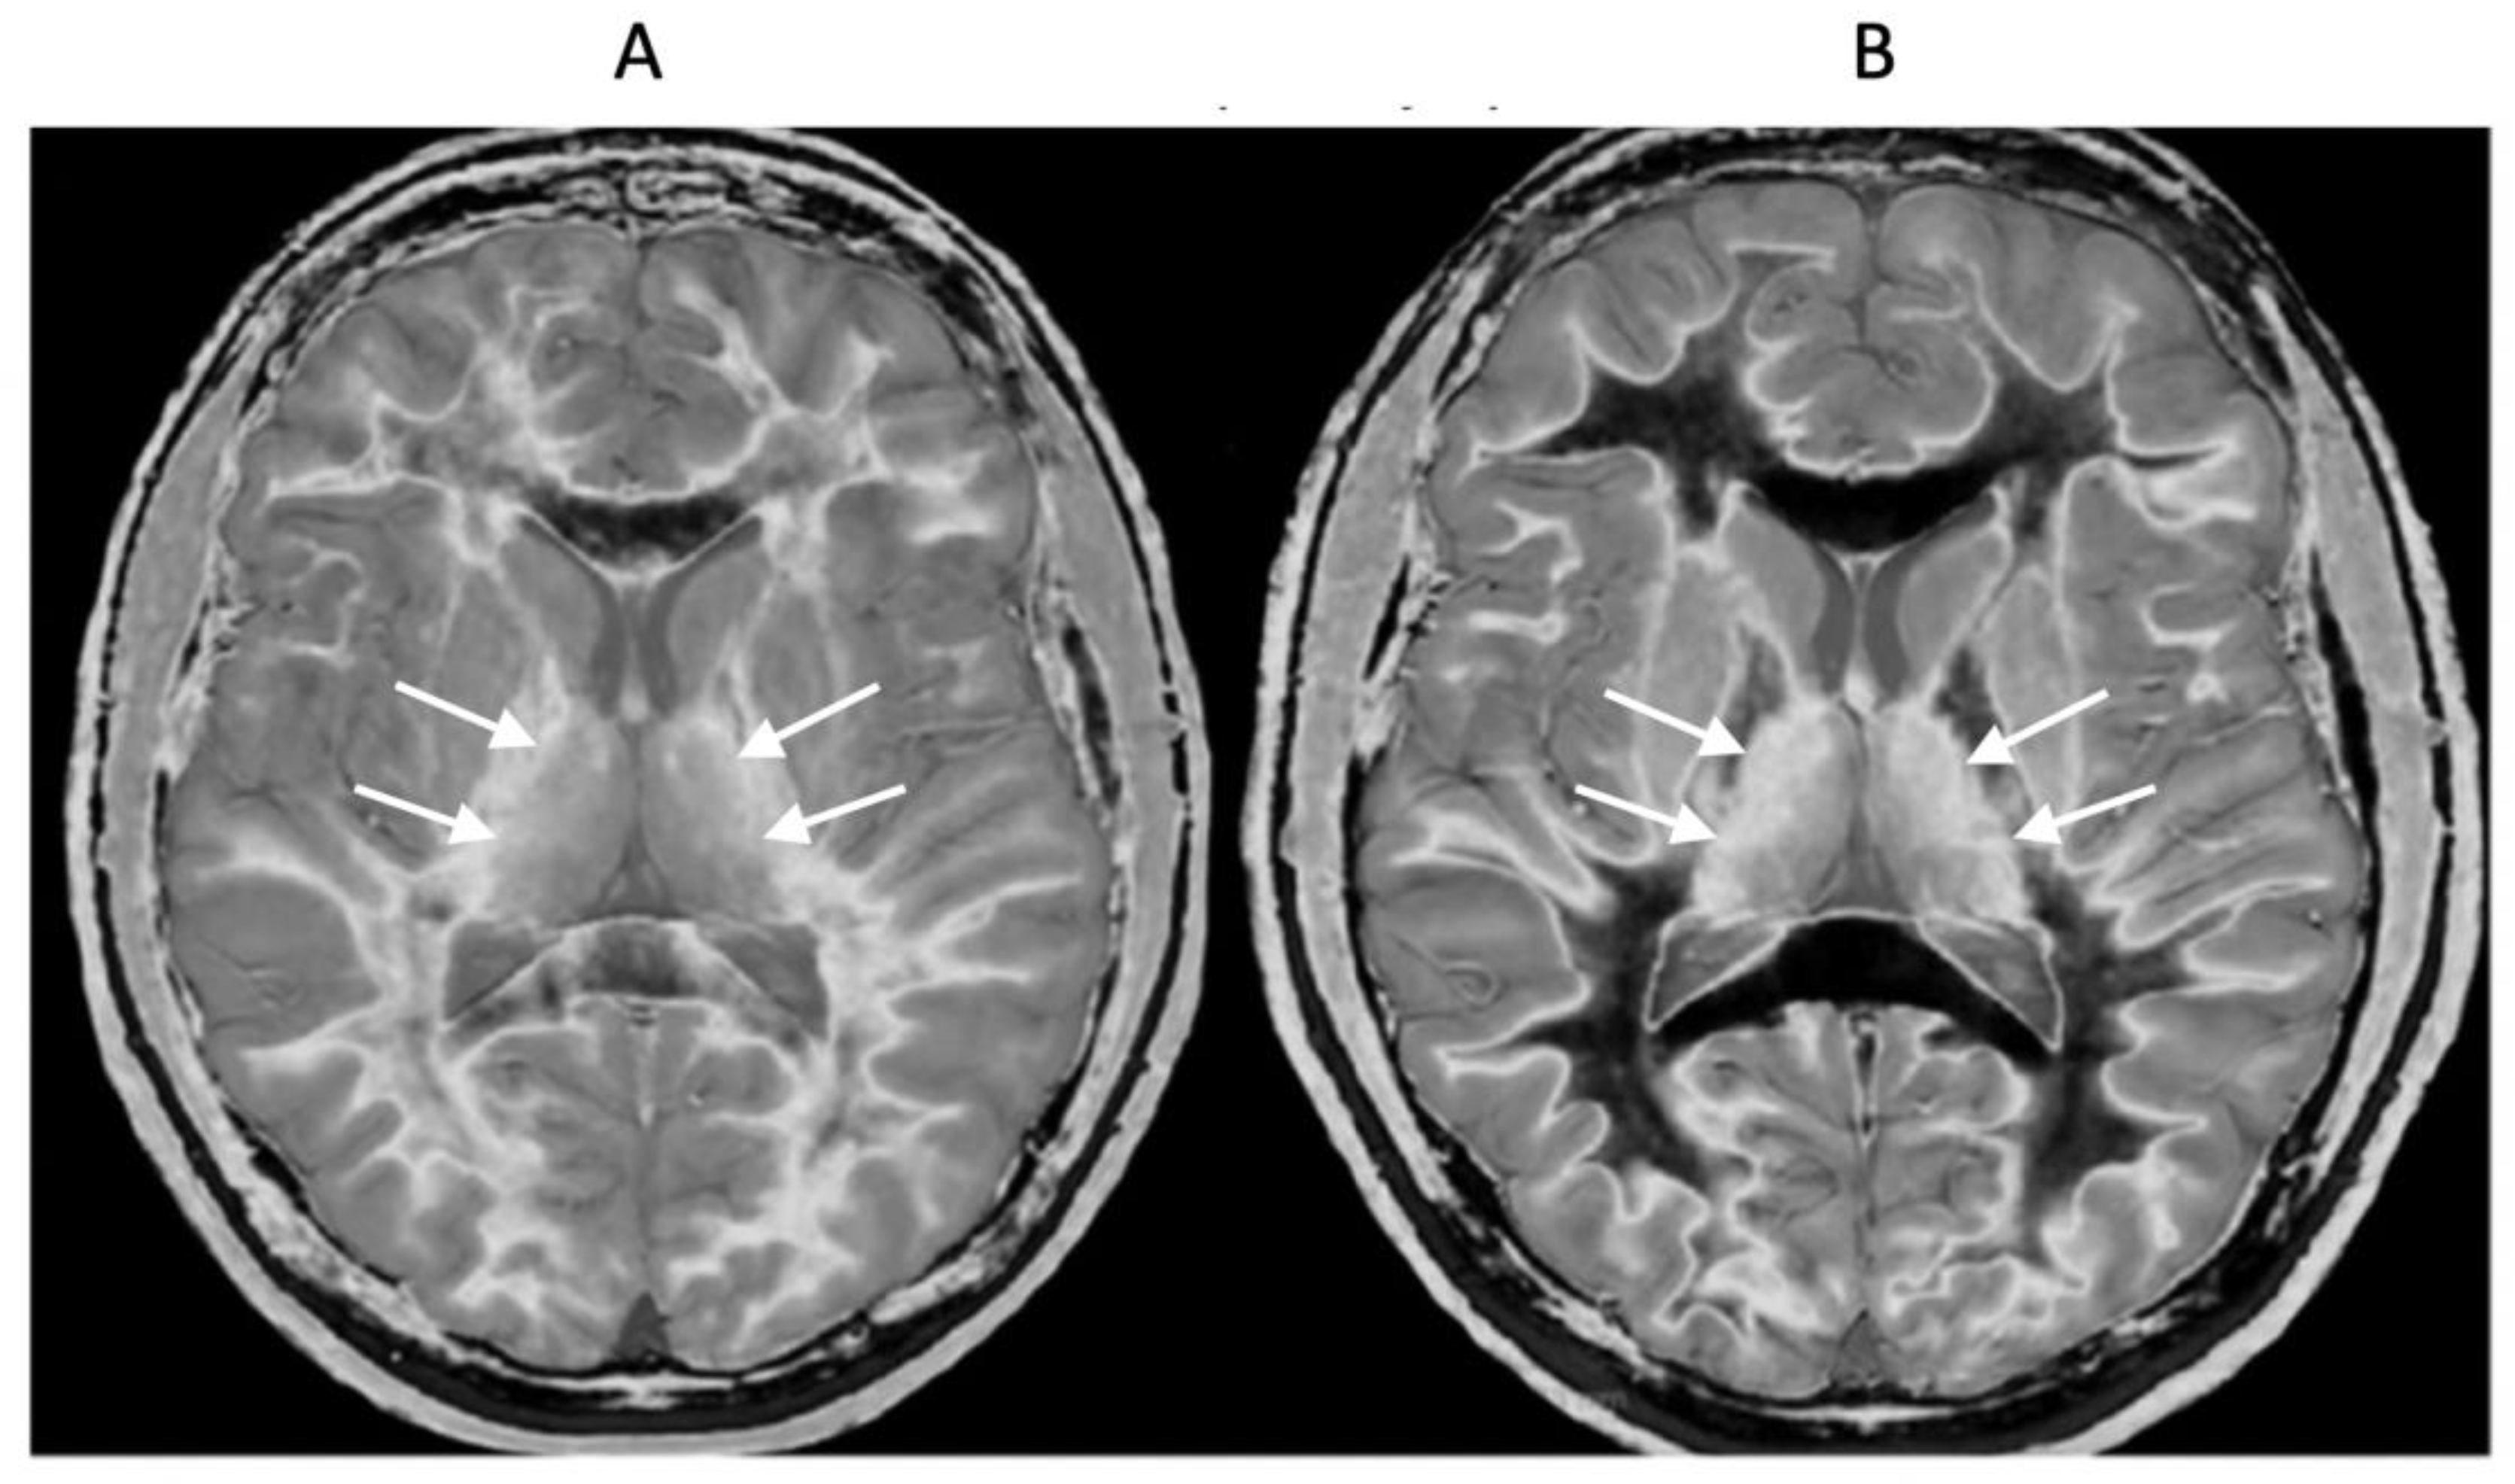

In addition to the whiteout sign, there may be loss of contrast in the gray matter of the thalamus due to an increase in T

1. This is manifest as a low contrast appearance between the medial and lateral thalamus (

Figure 12A) (arrows) (a grayout sign). After remission normal high gray white matter contrast is restored (

Figure 12B) (arrows). Contrast between the lateral thalamus (arrows) and the posterior limb of the internal capsule (PLIC) is low in (

Figure 12A) but very high in (

Figure 12B). The low contrast between the thalamus and the PLIC in (A) results from a reduction in signal in the gray matter of the lateral thalamus due to an increase in its T

1 in the hD as well as an increase in signal in the white matter of the PLIC due to an increase in its T

1 in the mD. This is reversed in (

Figure 12B) where the normal high contrast boundary is restored.